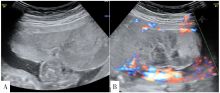

图2 病例3孕31<sup>+6</sup>周绒毛膜板下出血

注:A为胎盘前方近子面可见偏高回声,为绒毛膜板下出血,范围长径达11.5 cm,与正常胎盘组织有分界,有分层;B为中央型前置胎盘,绒毛膜板下出血位于胎盘脐带插入点附近;C为胎儿外生殖器呈"郁金香征";D为左侧子宫动脉可见切迹;E为出生后胎盘大体可见胎盘子面胎膜(羊膜+绒毛膜)与胎盘实质有分离,胎盘娩出过程中曾在其间积聚的不凝血已流失;F为出生后外生殖器证实为尿道下裂